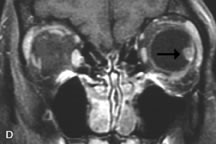

On MRI, uveal melanomas have a typical appearance that helps to differentiate them from other primary and secondary intraocular tumors as well as choroidal detachments. Pigmented melanomas are hyperintense on Tl-weighted images, hypointense on T2-weighted studies, and hyperintense on proton density–weighted examinations (Fig. 24).30,31,50,80–82 These signal characteristics have been attributed to the paramagnetic properties of melanin because of stable free radicals that shorten the T1 and T2 relaxation times. Moderate enhancement is seen on postgadolinium T2-weighted images. Gadolinium-enhanced T1-weighted images are particularly sensitive in detecting choroidal melanomas.83 MRI may be less sensitive in detecting extrascleral extension of tumor than echography performed by an experienced ultrasonographer.84

Fig. 24. A. T1- and (B) T2-weighted MR scans demonstrate a small nodular intraocular mass (arrows) that is very hyperintense on the T1-weighted scan and hypointense on the T2-weighted image. This signal intensity pattern is due to the presence of free radicals within melanin granules. C and D. Postcontrast fat-suppressed T1-weighted scans demonstrate homogeneous intense enhancement of the lesion and no evidence of seleral penetration or optic nerve invasion.